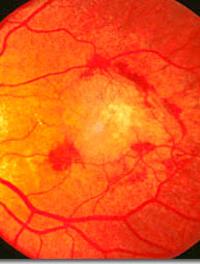

Une équipe de chercheurs a récemment publié dans JAMA Ophtalmology, les résultats à 12 mois de l’étude EVEREST II, dont l’objectif [...]

La dégénérescence maculaire liée à l’âge (DMLA) est la principale cause de malvoyance chez les plus de 50 ans en Europe et en Amérique [...]

La dégénérescence maculaire liée à l’âge est extrêmement fréquente, elle est systématiquement l’une des trois premières causes de cécité [...]